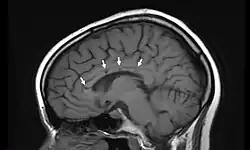

Sagittal T1 image in a 19-year-old woman with Susac's syndrome showing the pathognomonic central callosal "holes" (microinfarcts) of SS. These residual "holes" (and sometimes, "spokes") develop as the acute callosal changes resolve.

In a recent analysis (Susac et al., 2003), MRI images from 27 patients fulfilling the diagnostic criteria of Susac's syndrome were reviewed. Multifocal supratentorial lesions were present in all patients. Most lesions were small (3 to 7 mm), though some were larger than 7 mm. All 27 patients had corpus callosum lesions. These all had a punched-out appearance on follow-up MRI. Though most commonly involving white matter, many patients also had lesions in deep grey matter structures, as well as leptomeningeal enhancement. Multiple sclerosis (MS) and acute disseminated encephalomyelitis (ADEM) can mimic the MRI changes seen in patients with Susac's syndrome. However, the callosal lesions in Susac's syndrome are centrally located. In comparison, patients with MS and ADEM typically have lesions involving the undersurface of the corpus callosum. Deep gray matter involvement commonly occurs in ADEM but is very rare in MS. Leptomeningeal involvement is not typical of either MS or ADEM: if 10 lesions are found in the brain of an MS patient, a lesion may be found in the corpus callosum. If a Susac patient has 10 lesions, more than half will be in the corpus callosum.